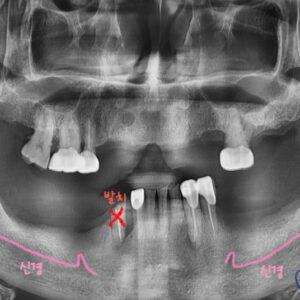

치료 계획을 세워 봅니다.

치아 뿌리를 제거하고, 전체 틀니 사용하기

치아 뿌리를 제거하고, 4개의 임플란트 식립 후, [임플란트 + 틀니]로 사용하기

치아 뿌리를 제거하고, 7개의 임플란트 식립 . (틀니 사용 X)

세가지의 옵션이 있습니다.

3번 옵션을 선택합니다.

7개의 임플란트를 식립하여, 틀니 사용을 하지 않기로 합니다.

다행히 잔존골이 풍부한 상태라, 큰 어려움 없이 임플란트를 식립합니다.